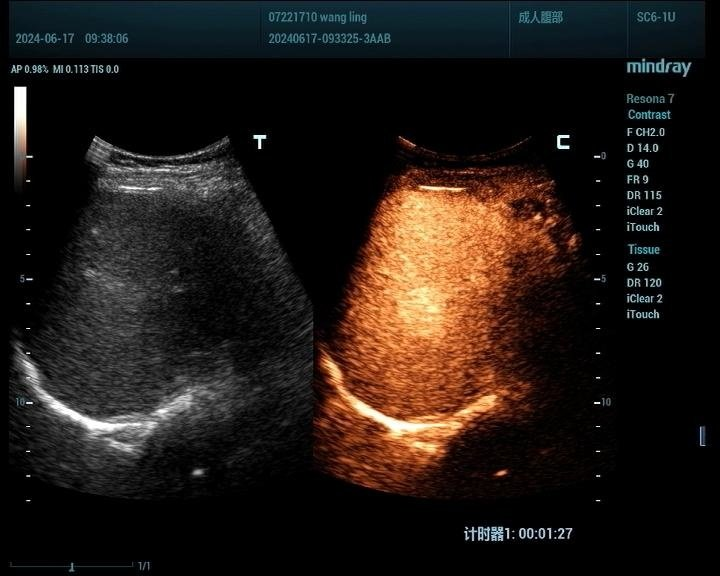

肝脏肿瘤分为良性和恶性,其中血管瘤是最常见的肝脏良性肿瘤,肝癌是最常见的恶性肿瘤。肝脏肿瘤超声影像诊断方面主要有肿瘤病灶的检出、对已检测肿瘤的定性诊断、肝局灶性病灶中肿瘤与非肿瘤病变的鉴别。超声造影对肝脏肿瘤的鉴别诊断主要是通过增强和动态增强方式观察肿瘤。

肝癌病例2